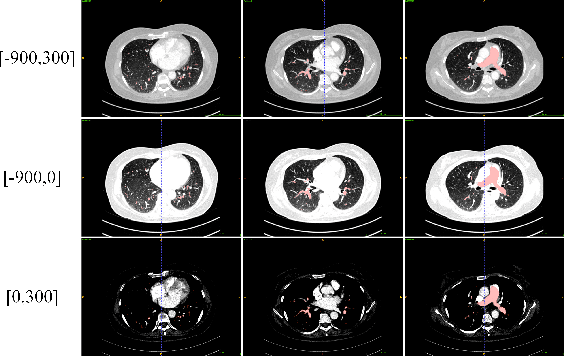

Abstract:This is the technical report of the 9th place in the final result of PARSE2022 Challenge. We solve the segmentation problem of the pulmonary artery by using a two-stage method based on a 3D CNN network. The coarse model is used to locate the ROI, and the fine model is used to refine the segmentation result. In addition, in order to improve the segmentation performance, we adopt multi-view and multi-window level method, at the same time we employ a fine-tune strategy to mitigate the impact of inconsistent labeling.